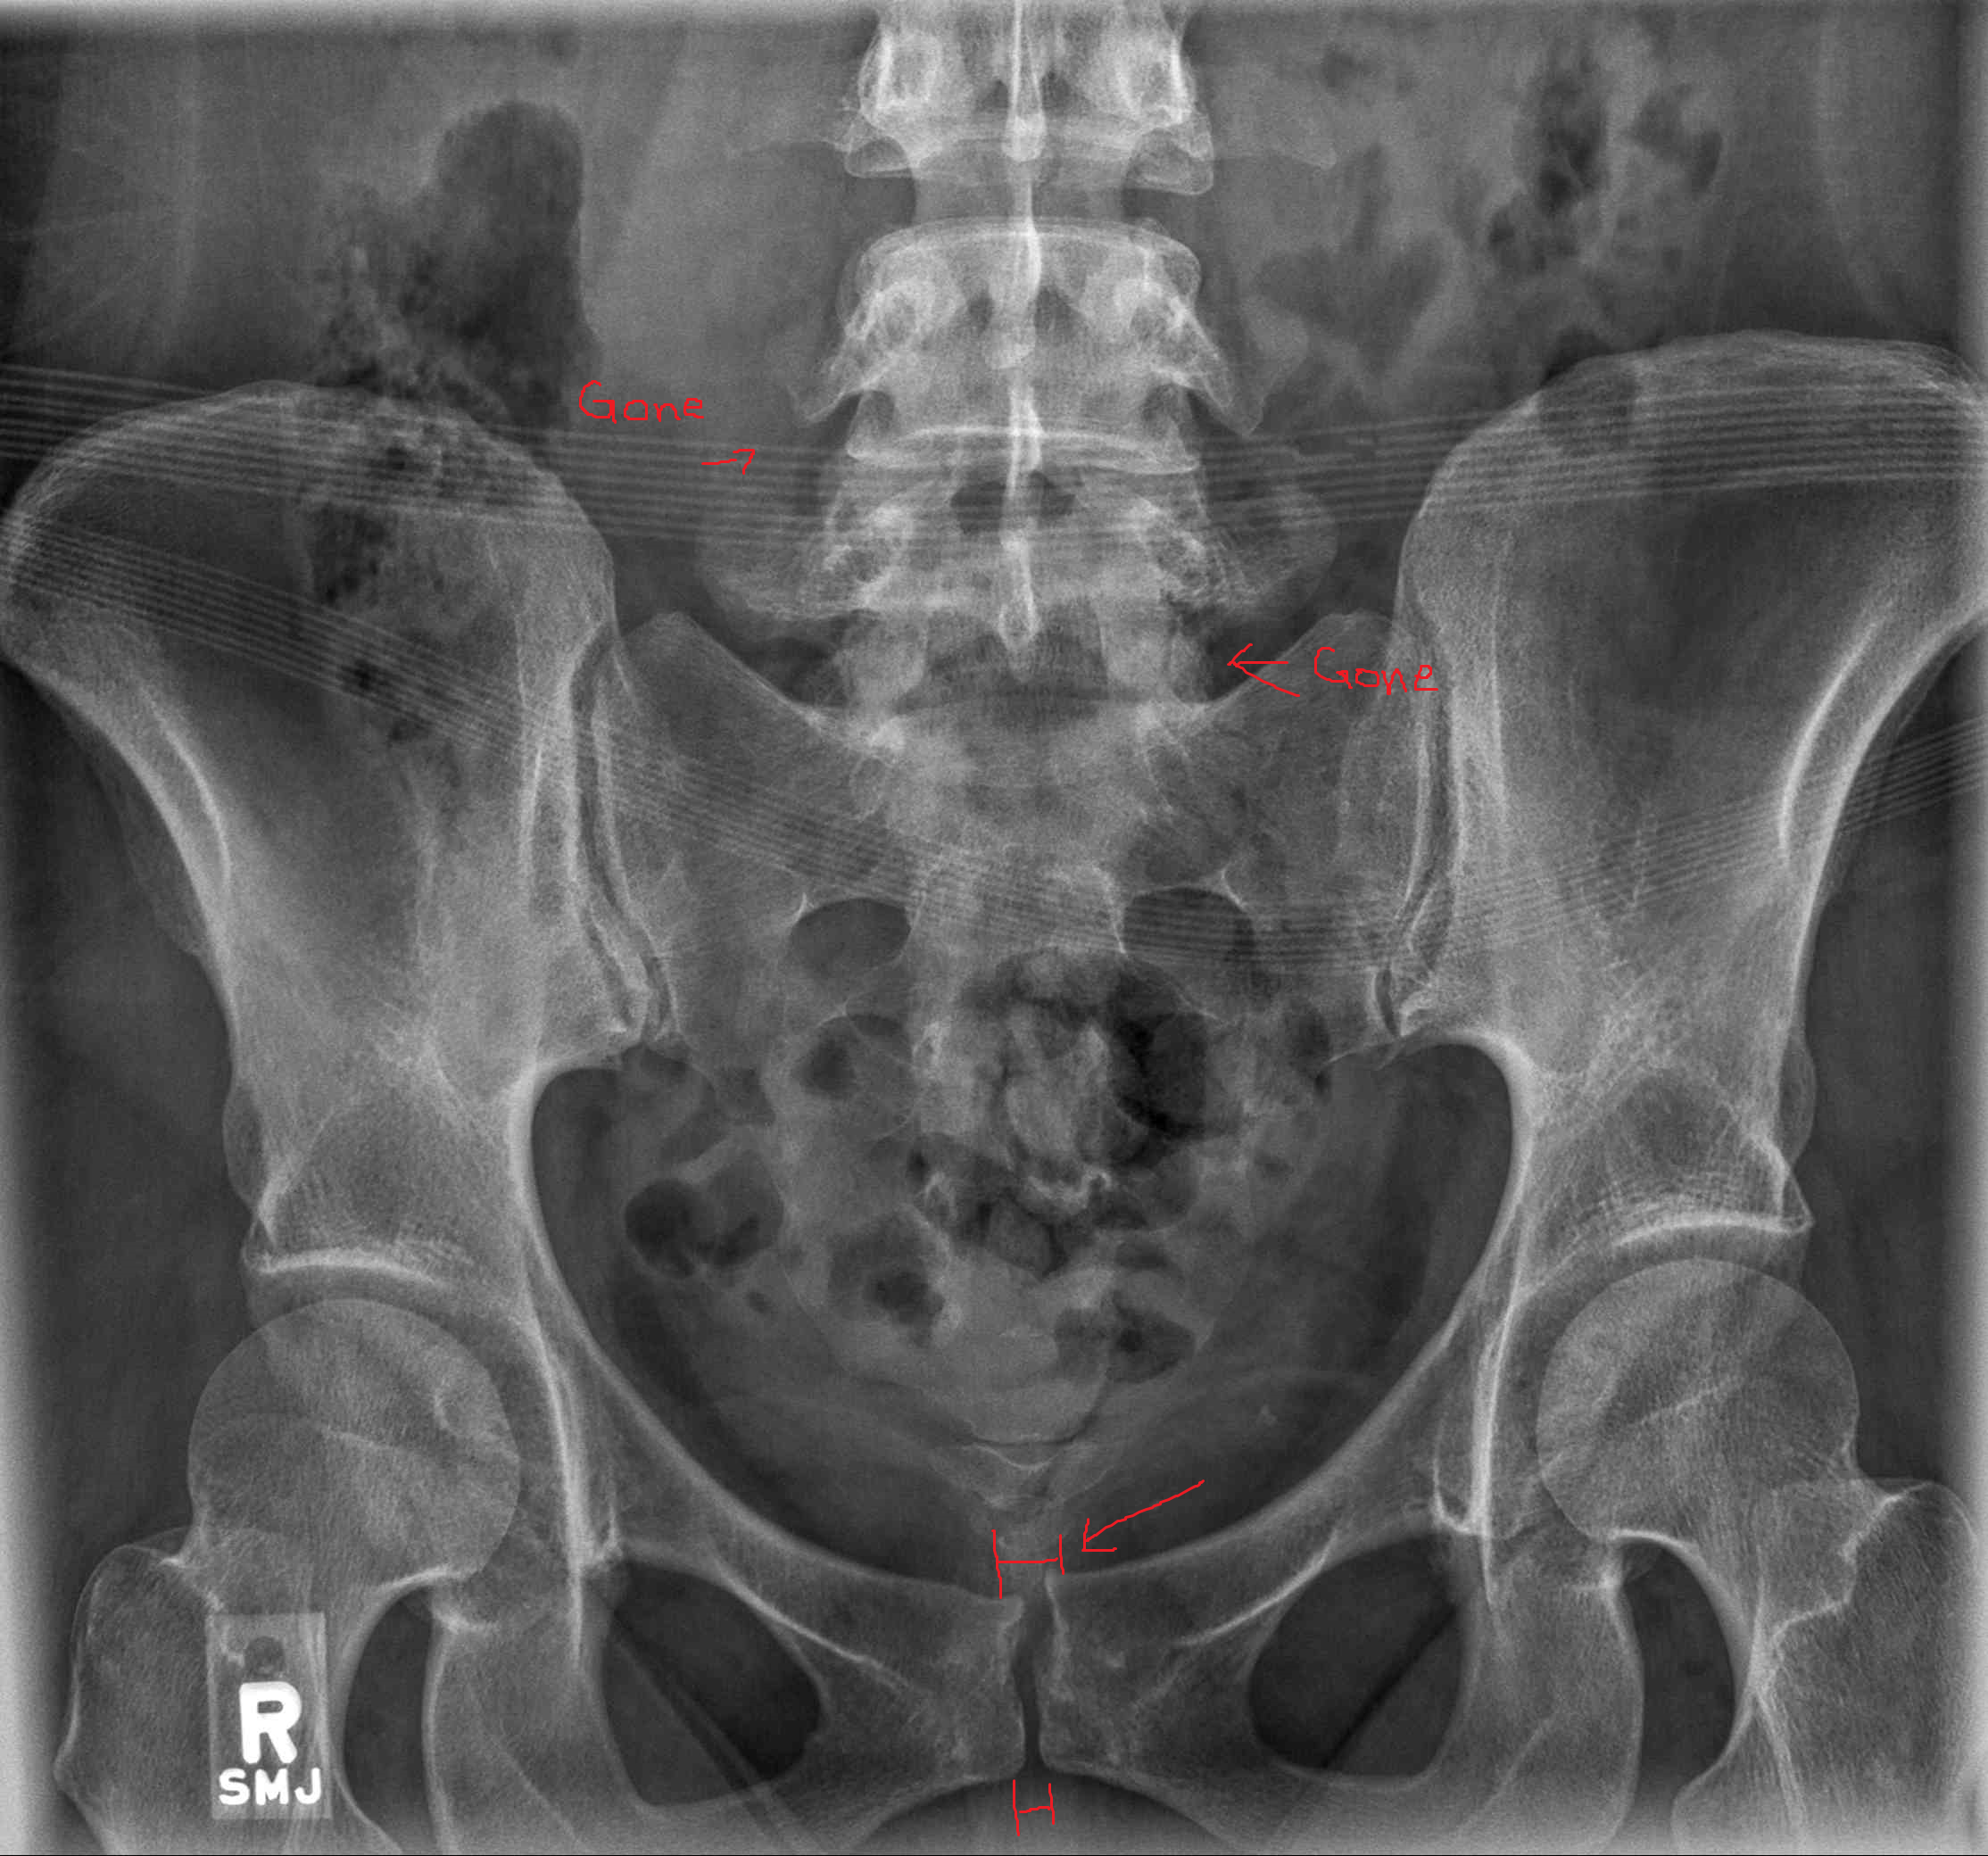

Hi, my name is Alex. There is a photo of me in a dress before everything happened. There is also a photo of the aftermath of living here. I’m currently living in a hostile and unsanitary environment that’s taking a serious toll on my health and well-being. I’m unable to work due to a pelvis and back injury shown in the x-ray. I’m trying to raise funds to relocate to a safer area where I can access proper medical treatment and begin healing—physically and emotionally.